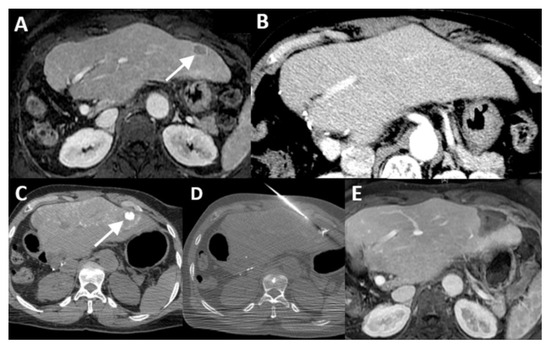

| 1 | 20 mm | Common hepatic artery | 15–20 mL Visipaque™ | Emprint™ Microwave Ablation System, Medtronic-Covidien, Boulder, CO, USA | MD Anderson, Houston, TX, USA |

| 2 | 20 and 7 mm | Common hepatic artery | 4 mL Xenetix 300® | Cool-tip™ RFA Ablation Aystem, Medtronic-Covidien, Boulder, CO, USA | Gustave Roussy, Villejuif, France |

| 3 | 12 mm | Left-sided hepatic artery | Not specified | Cool-tip™ RFA Ablation System | Gustave Roussy |

| 4 | 9 mm | Common hepatic artery | 10 mL Xenetix 300® | Emprint™ Microwave Ablation System | Amsterdam UMC, Amsterdam, The Netherlands |

| 5 | 15 mm | Coeliac trunk | 20 mL Xenetix 300® | Emprint™ Microwave Ablation System | Amsterdam UMC |

| 6 | Not applicable | Common hepatic artery | 20 mL Xenetix 300® | Emprint™ Microwave Ablation System | Amsterdam UMC |

| 7 | Confluent | Common hepatic artery | 10 mL Xenetix 300® | NanoKnife system under ECG-gating; AccuSync model 72, AngioDynamics, Latham, NY, USA | Amsterdam UMC |

| 8 | 15 mm | Common hepatic artery | 15–20 mL Visipaque™ | Emprint™ Microwave Ablation System | MD Anderson |